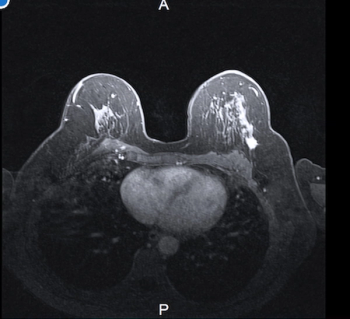

Additional carcinoma in the ipsilateral breast was detected on preoperative MRI exams in 24 out of 102 women prior to lumpectomy and mastectomy procedures, according to new study findings presented at the 2024 American Society of Clinical Oncology (ASCO) Annual Meeting in Chicago.

In a study of over 2,000 women with dense breasts and average breast cancer risk, abbreviated MRI (AB-MR) demonstrated an 18.9 per 1000 cancer detection rate (CDR) in baseline exams, and all cancers detected with baseline or subsequent AB/MR exams were stage 0 or 1.